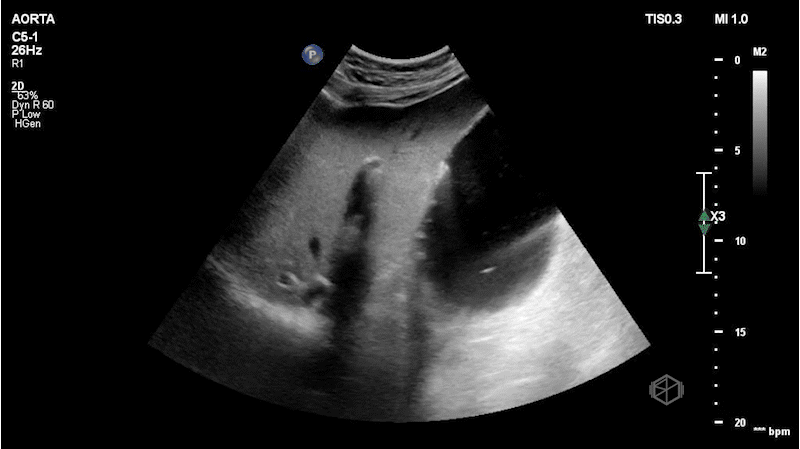

The first SonoProps goes to our current resident rotator Dr. Antonia Nevias-Ida.

She was scanning a 55-year-old female with LEFT flank pain that came on sudden onset and captured the following images:

If you are thinking this is positive for free fluid — surprise — it is not!

It is actually an artifact called lipliner sign. Free fluid generally makes sharp angles and persists throughout multiple views, where as this anechoic stripe disappears as the probe position is varied.

Diagnosis: Lipliner sign

• There are many misleading artifacts and false positives to consider when performing a FAST/FAFF examination including focal fatty sparing, double line sign, and now the lipliner sign.

• Lipliner sign is an artifact that appears at the edge of solid organs such as the liver or the spleen (the more common areas for free fluid) (39366788) and can easily mislead a clinician to assume there is free fluid present.

• It is not definitively known what causes the lipliner sign but it may be due to advances in ultrasound machines likely due to adaptive filtering to improve spatial resolution and post-processing technology.

• The artifact may be visible on machines from multiple manufacturers.

• When encountering lipliner artifact and deciding it may be reasonable to call the FAST equivocal rather than a true positive if there is any question.

• True free fluid makes sharp angles, dissects through structures, is dependent, should not have any membranes or walls, and is dynamic (eg, place the patient in Trendelenburg and more fluid will shift up).